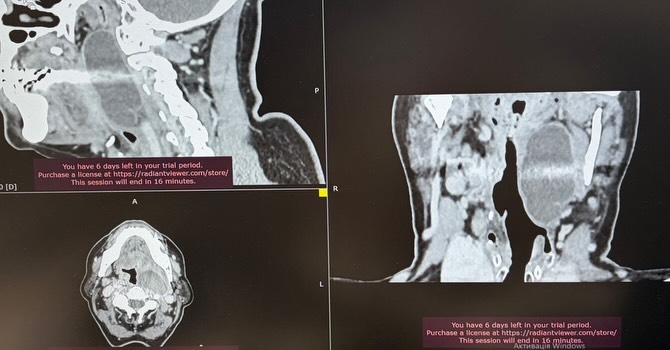

Хірурги Подільського регіонального центру онкології провели надскладну операцію на парафарингеальному (позаглотковому) просторі. Через рідкісну локалізацію та близькість до життєво важливих судин, пухлина загрожувала диханню пацієнтки. Завдяки точному плануванню та професіоналізму медиків, новоутворення вдалося видалити повністю, повернувши жінці можливість вільно жити.

Пухлини цієї локалізації трапляються відносно нечасто. Вони можуть тривалий час залишатися майже непомітними, однак зі збільшенням розмірів починають викликати виражені симптоми через близькість до важливих анатомічних структур.У даному випадку пухлинне утворення досягло значних розмірів і почало утруднювати прийом їжі та дихання, що потребувало оперативного лікування.

Зважаючи на анатомічну складність цієї ділянки та близькість магістральних судин і нервових структур, лікарі провели ретельне передопераційне планування. Операція була виконана у плановому порядку, і пухлинне утворення вдалося повністю видалити.